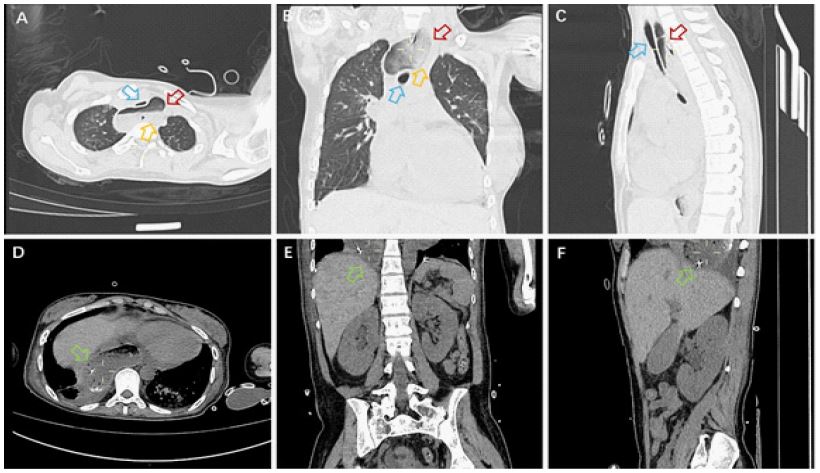

A 24-year-old female was admitted to the hospital due to muscle soreness in the limbs, retrosternal pain, and difficulty swallowing for over 50 days. Upon admission, physical examination revealed proximal muscle strength of level 3 in both upper limbs and level 5 in distal muscles, proximal muscle strength of level 4 in both lower limbs and level 5 in distal muscles, with no muscle atrophy or pseudohypertrophy observed, and normal muscle tone. Laboratory tests indicated that creatine kinase 4474 U/L, lactate dehydrogenase 330 U/L, interleukin-6 266.94 pg/ml, erythrocyte sedimentation rate 38 mm/h. The idiopathic inflammatory myopathy profile revealed a nucleolar-pattern Antinuclear Antibody (ANA) titer of 1:100 and strongly positive anti-NXP2 IgG antibodies (+++). Electromyography suggested possible myogenic damage, and chest CT indicated dilation of the upper esophagus with contents, measuring up to 5.6 centimeters at its widest point. Abdominal CT showed a gas-containing stomach sac above the diaphragm, suggesting a hiatal hernia (Figure 1). The patient was diagnosed with dermatomyositis, considering the esophageal dilation and hiatal hernia as manifestations of dermatomyositis in the digestive tract. After treatment with prednisone, methotrexate, and tocilizumab, the patient’s symptoms gradually improved.